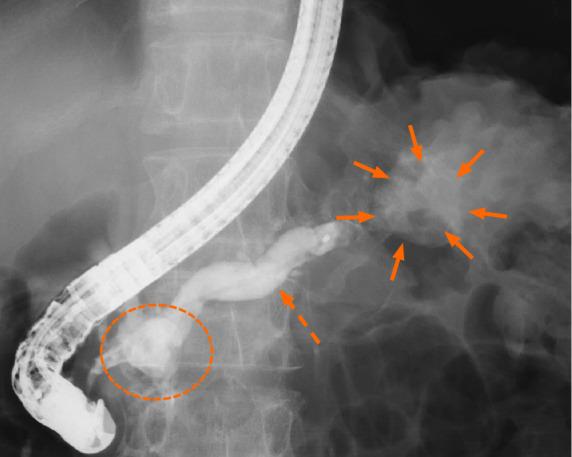

A 62-year-old male with a 10-year history of chronic pancreatitis presented with epigastric pain for one week and a 20 kg weight loss over one year. Computed tomography showed stones in the pancreas (mainly the head), expansion of the main pancreatic duct, and thinning of the pancreatic parenchyma. Magnetic resonance imaging showed infected pancreatic cysts connected to the stomach with a fistula from the splenic hilum to the caudal portion of the liver's lateral segment. An endoscopic retrograde pancreatography was performed; the guide wires could not pass through the stones in the pancreas and therefore, drainage of the main pancreatic duct was not achieved. Next, a distal pancreatomy and splenectomy were performed; however, the pancreatic juice in the remaining parenchyma was blocked by the stones. Hence, we performed a retrograde pancreatojejunostomy and Roux-en-Y anastomosis. The patient had no postoperative complications and was discharged from the hospital on postoperative day 14.

一名62岁男性,有10年慢性胰腺炎病史,出现上腹部疼痛1周,1年内体重减轻20公斤。计算机断层扫描显示胰腺(主要是头部)有结石,主胰管扩张,胰腺实质变薄。磁共振成像显示感染性胰腺囊肿与胃相连,脾门至肝外侧段尾状部有瘘管。进行了内镜逆行胰胆管造影;导丝无法穿过胰腺内的结石,因此未实现主胰管引流。接下来,进行了胰体尾切除术和脾切除术;然而,剩余实质内的胰液被结石阻塞。因此,我们进行了逆行胰空肠吻合术和Roux-en-Y吻合术。患者术后无并发症,术后第14天出院。